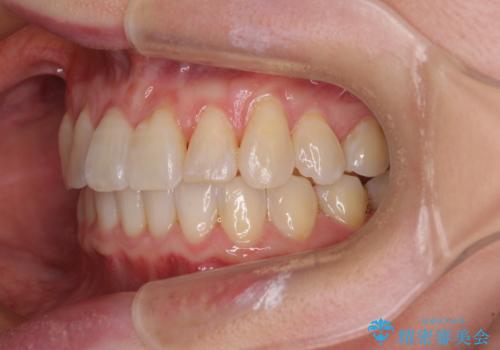

前歯のクロスバイト インビザライン矯正で改善

- むし歯治療を契機に、長年気にしていた前歯のクロスバイトの改善を希望された患者様です。

汚れが溜まりやすく、歯ぎしりがうまくできないため、インビザラインを用いて矯正治療を行うこととしました。

インビザラインによる前歯のクロスバイトの改善は、治療期間中に前歯でしか咬めない時期が続いたり、歯肉退縮や歯髄壊死のリスクが高まったりと、治療中にトラブルを抱えることがあります。

特に上顎側切歯(真ん中から2番目の歯)が舌側に引っ込んでいるケースは、インビザラインでは改善しきれないことがあると言われています。